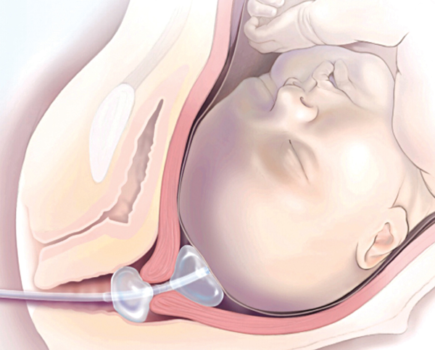

Quá trình chuyển dạ sẽ khác nhau ở mỗi thai phụ. Hầu hết cuộc sinh...